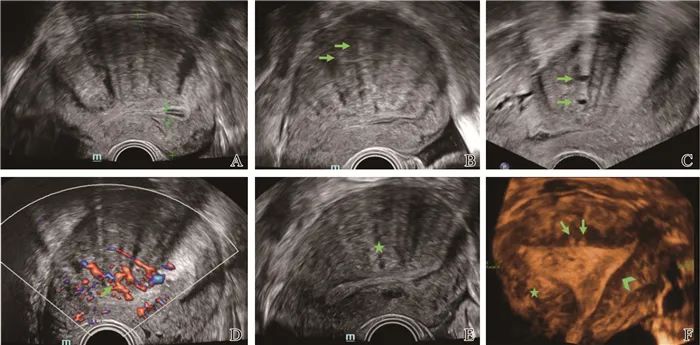

在妇科领域,刘富发运用肘搓八髎术,10秒30次高频共振,可穿透至盆腔纾解粘连。

一名子宫腺肌症患者经十几次的调理后,病痛消失。

这一案例不仅让患者重获健康,更让肘滚技法在妇科领域也大放异彩。